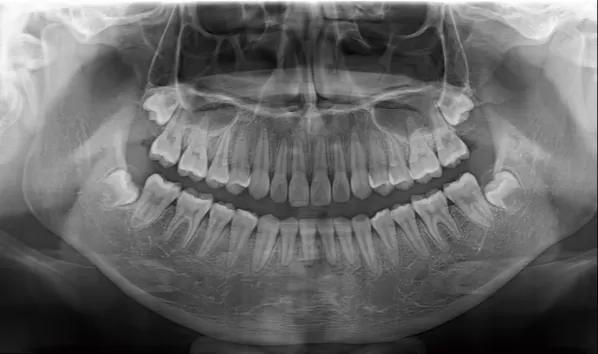

X-rays before treatment

[Panoramic Radiography/Lateral Cephalogram]